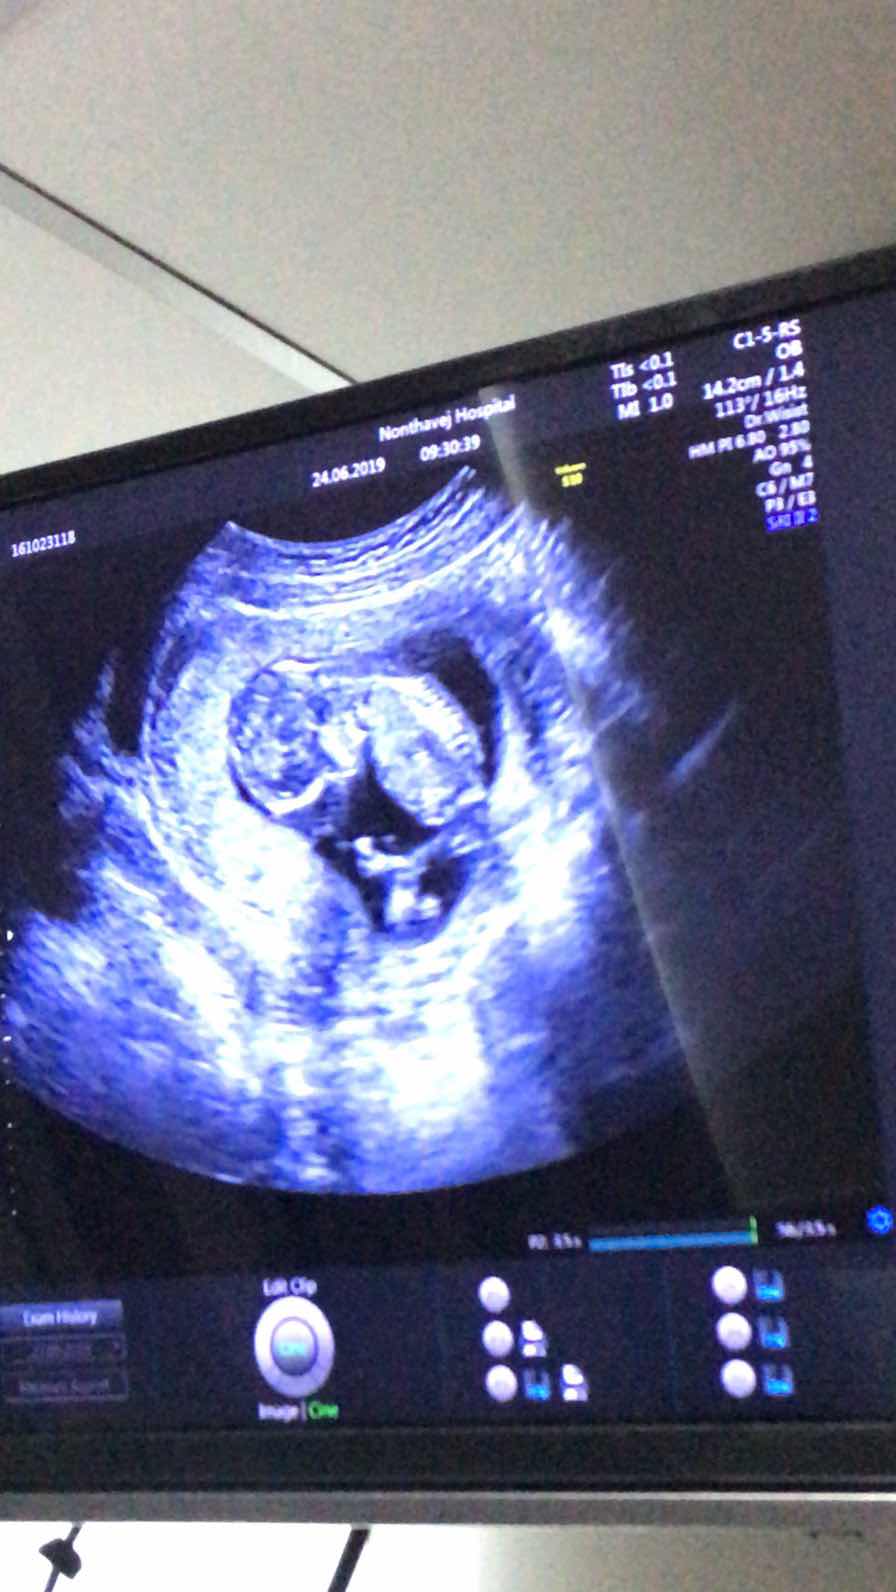

13wค่ะ